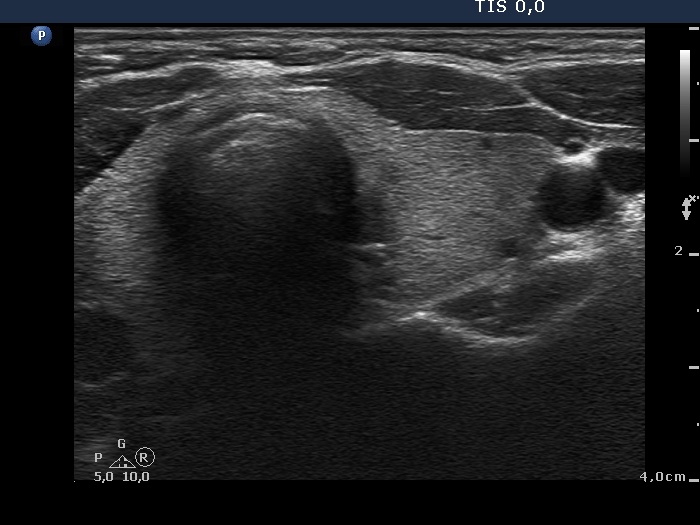

Initial examination (first row of images):

Clinical presentation: A 39-year-old woman was referred for evaluation of neck complaints lasting for more than a month. The patient had fever, neck pain. She has got two courses of antibiotics and non-steroid anti inflammatory drugs which had no effect.

Palpation: The right lobe was painful and hard while the left lobe was tender.

Laboratory examination: TSH 0.01 mIU/L, FT4 29.1 pM/L, FT3 7.45 pM/L, CRP 31.2 mg/L.

Ultrasonography: The thyroid presented with hypoechoic areas which had blurred borders. The echogenicity index was approximately 65% in the right and 20% in the left lobe. The thyroid was almost completely avascular.

Diagnosis: subacute, granulomatous de Quervain's thyroiditis.

Suggestion. Steroid therapy was suggested.